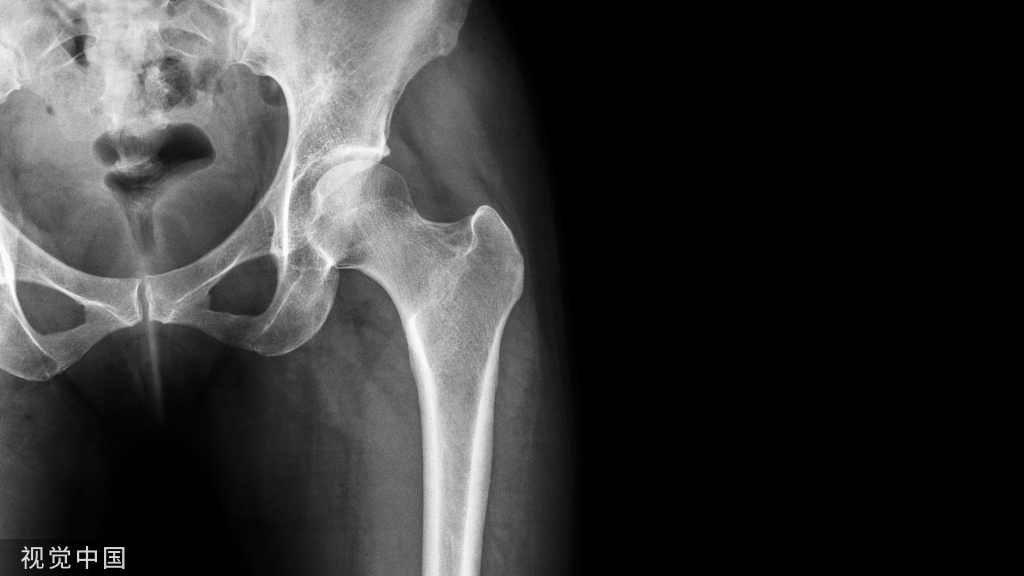

胫骨 pilon 骨折的发生多是由于高能量轴向负荷产生的关节和干骺端粉碎以及广泛的软组织损伤。腓骨骨折的存在是胫骨 pilon 骨折放射学严重程度的预测指标。

然而 ,关于胫骨pilon ORIF 中腓骨固定的作用报道不多,但越来越多的证据表明,在这些复杂骨折中,腓骨根本不需要固定。

胫骨 pilon 骨折治疗中的腓骨固定不是常规必需的,也不会减少机械并发症,如畸形愈合、延迟愈合、骨不连和植入物失败。腓骨骨折固定应保留用于可能有助于复位或提供额外稳定性的情况。需要更多的临床研究来探讨腓骨固定在治疗胫骨 pilon 骨折中的作用。